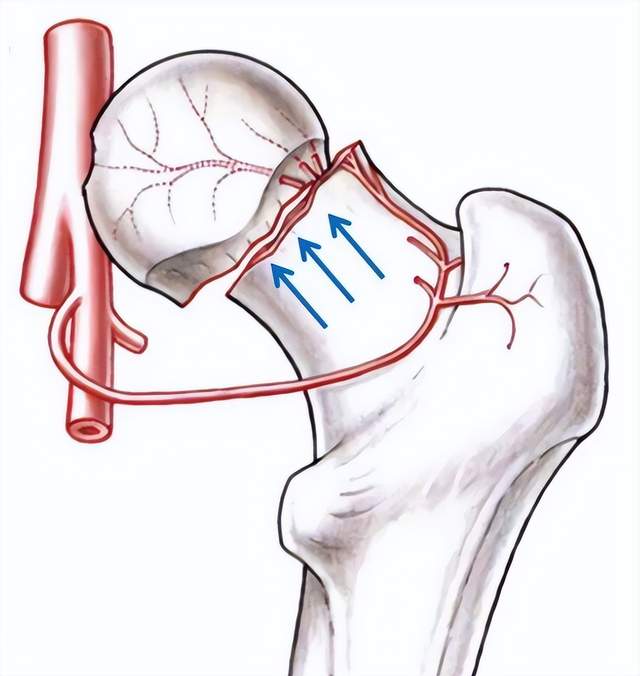

2.创伤性股骨头坏死

如因暴力撞击引起股骨颈骨折、髋关节脱位等,因为骨折及脱位影响了股骨头的血液供应,缺血的股骨头极易发生坏死。创伤性股骨头缺血坏死发生与否、以及范围的大小,主要取决于血管破坏程度和侧支循环的代偿能力。